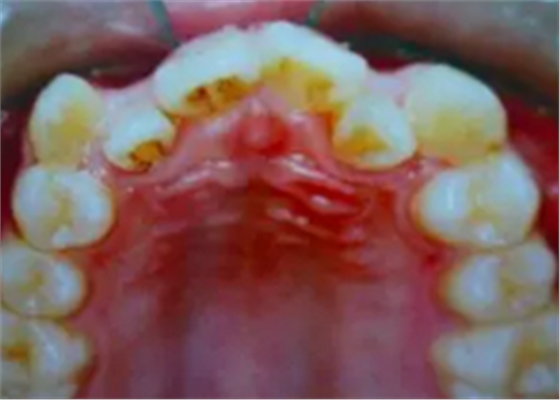

牙齒需要矯治的患者,往往牙齒和排列和咬合關(guān)系多會(huì)出現(xiàn)錯(cuò)亂,那些錯(cuò)亂的牙齒即使不拔除,它也是沒(méi)有功能的,因?yàn)樗蛯?duì)頜的牙齒咬不上。

并且,這些排列不正常的牙齒很難清理干凈,容易在它的周?chē)媪艉芏嗍澄餁埩?,久而久之就形成蛀牙,最后也是一拔了之。我們醫(yī)生拔牙的時(shí)候有一定選擇的,一般是拔除那些壞牙、沒(méi)有功能的牙。